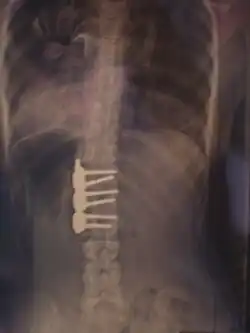

![]() Рентгеновский снимок позвоночника пациента со сколиозом с левосторонним искривлением в поясничном отделе и правосторонним искривлением в грудном отделе позвоночника. | |

Хирургическое лечение

При неуспехе бескровного консервативного лечения из-за нарушения предписанного режима ношения корсета, плохого качества изготовленного корсета или отказе от него рассматривается операция по установке металлических конструкций и аутотрансплантантов (небольших фрагментов кости таза пациента, превращённых в костную крошку) фиксирующих между собой тела позвонков, называемая «спондилодез» или «fusion»-закрепление(слияние, заваривание).

При оперативном лечении искривлённая часть позвоночника выпрямляется до определённого возможного угла при помощи металлических стержней и шурупов (т. н. транспедикулярных винтов), что ведёт к полному обездвиживанию этих отделов позвоночника. Операция при сколиозе подходит прежде всего для сильных искривлений, которые больше не могут лечиться другими методами. Оперативная фиксация может предотвратить дальнейшую прогрессию и ухудшение состояния.